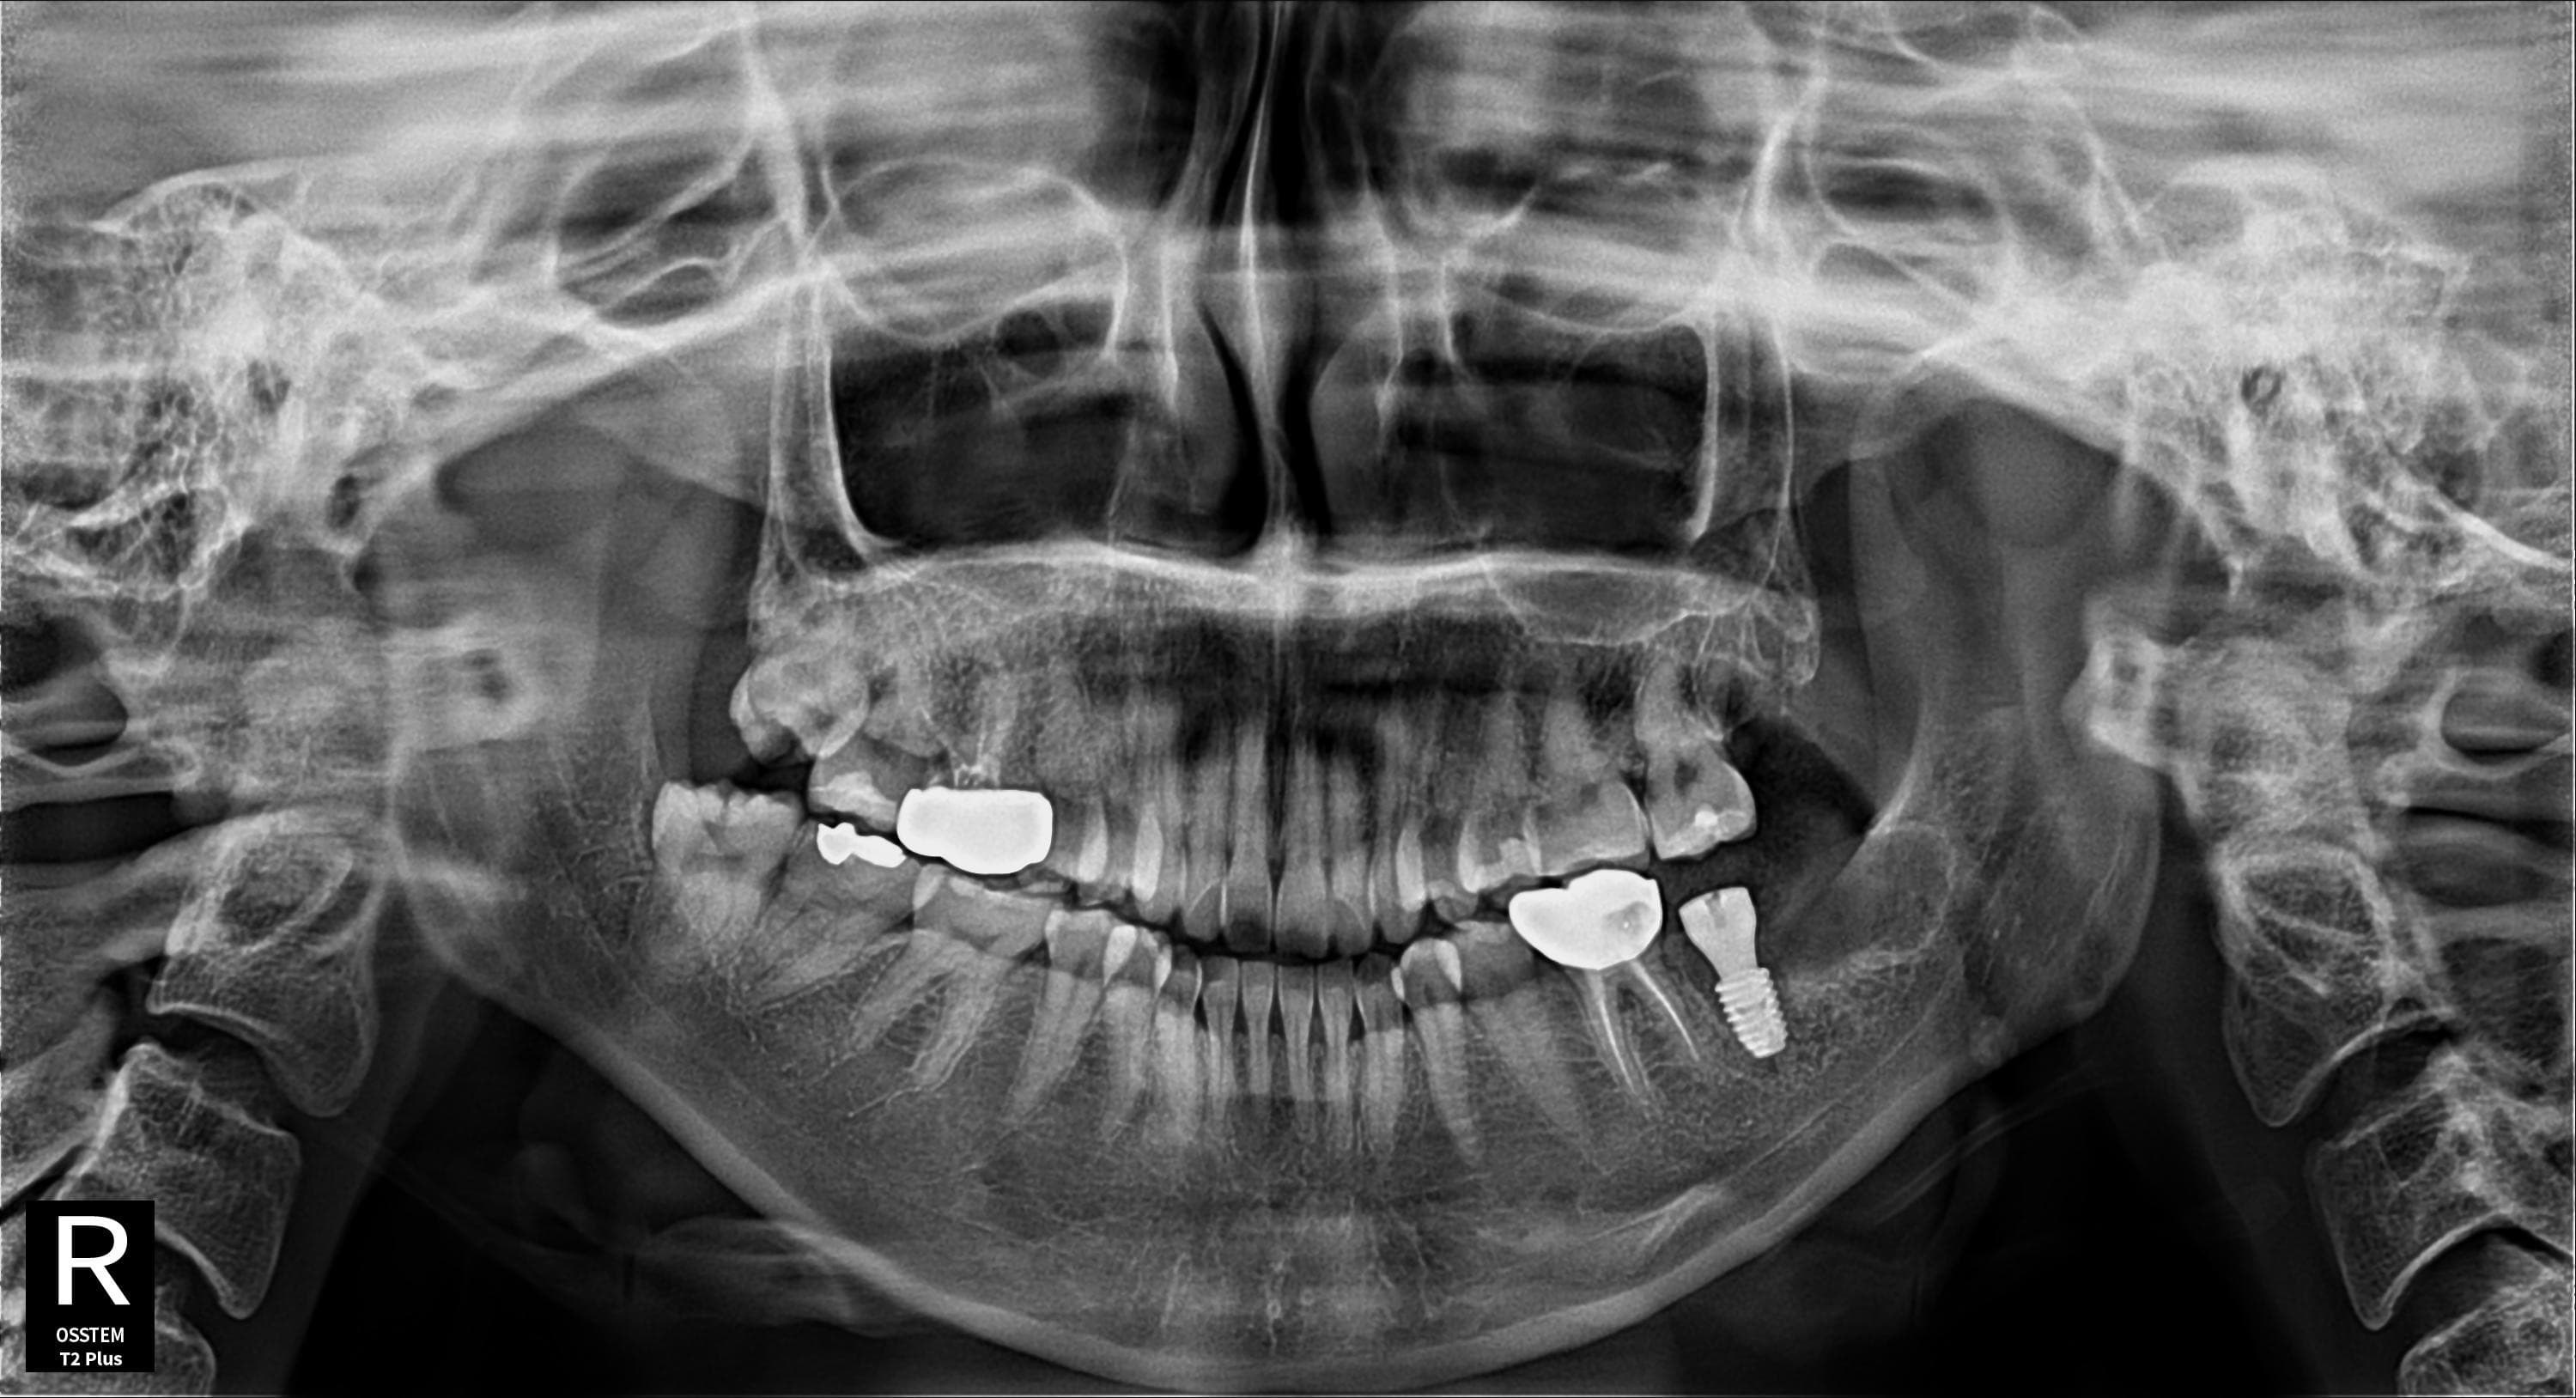

임플란트 + 사랑니 동시 시술

임플란트 식립과 사랑니 발치를 한번에

Before

After

임플란트 식립과 사랑니 발치를 동시에 진행하여 내원 횟수 최소화